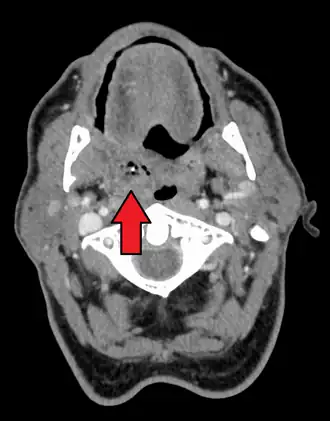

Peritonsillar abscess on the person's right as seen on CT imaging

Diagnosis is usually based on the symptoms.[1] Medical imaging may be done to rule out complications.[1] Medical imaging may include CT scan, MRI, or ultrasound is also useful in diagnosis.[1]